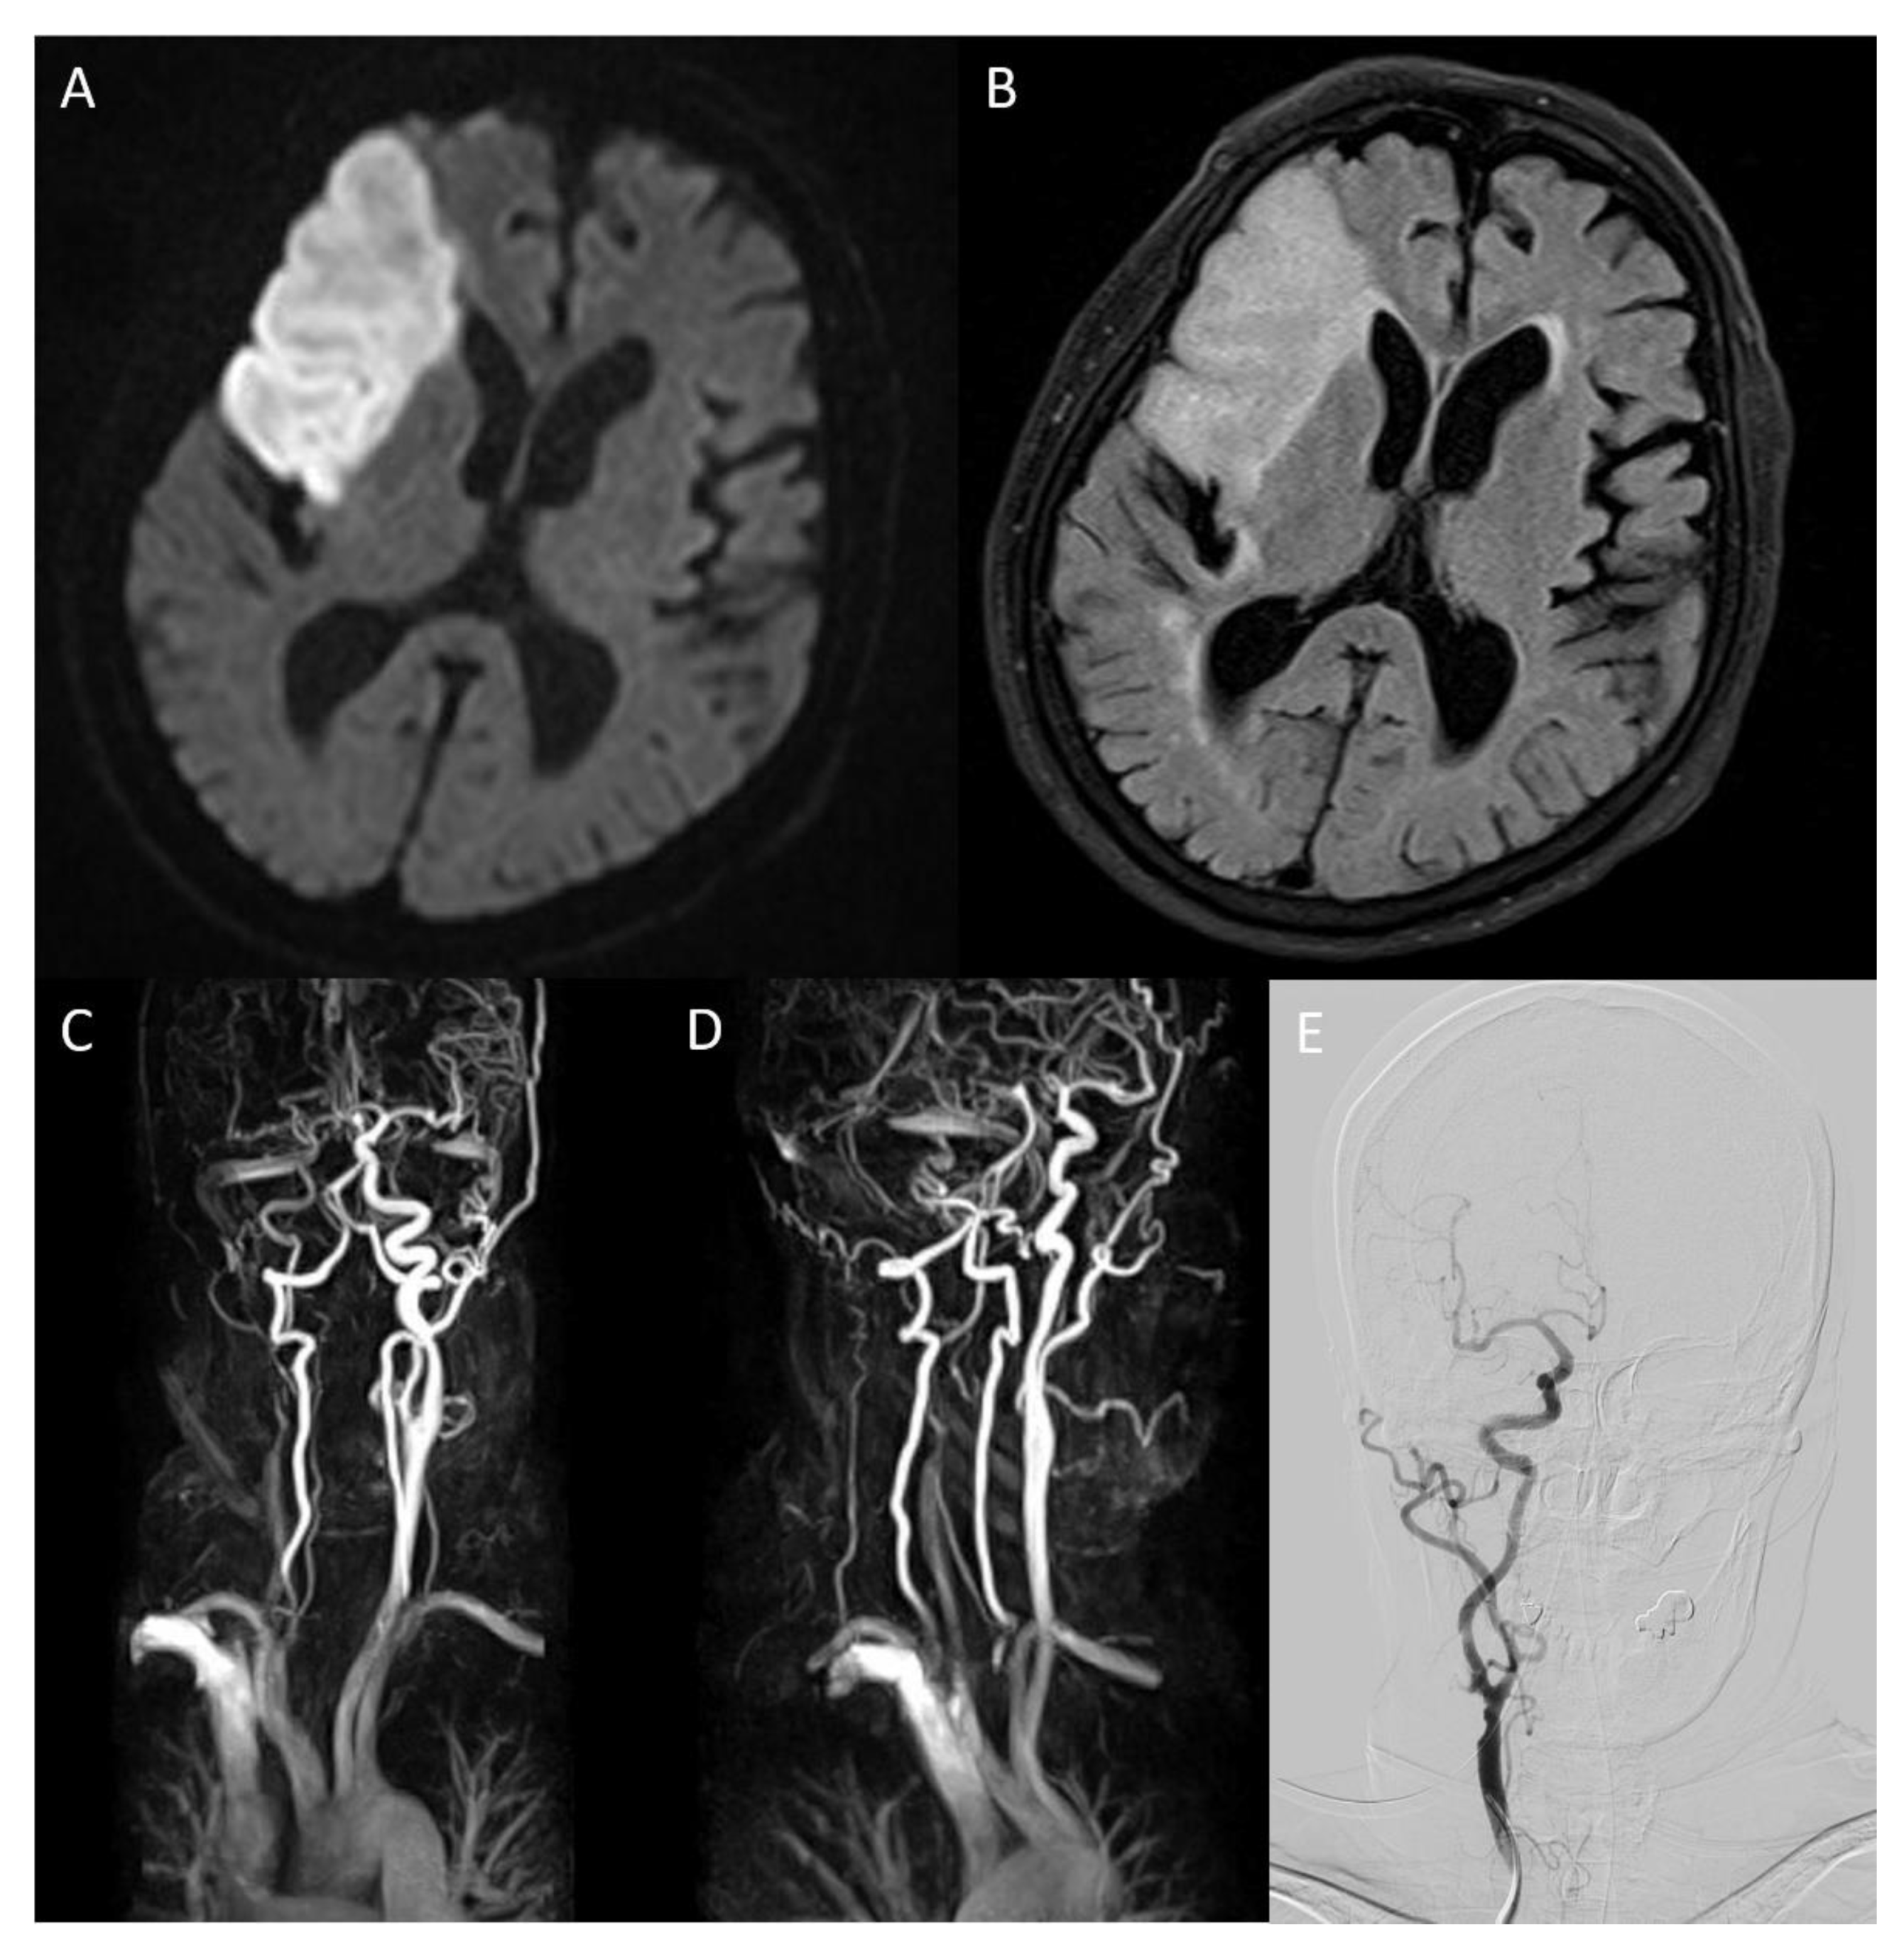

On the eighth day of hospitalization, the patient complained of dyspnea. Pleural effusion in the right lung was confirmed by follow-up chest X-ray, and the management for pleural effusion was initiated. On the eleventh day of hospitalization, carotid duplex ultrasonography showed extensive stenosis from the right carotid artery bulb to the proximal ICA (Figure 2). Peak systolic velocity (PSV) measured at the site of ICA stenosis was 214.4 cm/s, indicating moderate to severe grade stenosis (Figure 2). Although the patient needed (DSA) and carotid artery stenting to manage the symptomatic CAS, these procedures were delayed to the sixteenth day of hospitalization because of her aggravated general condition due to pleural effusion. On the right ICA angiogram of the DSA, the previously confirmed moderate to severe stenosis had almost regressed. Only mild stenosis with ulcerative plaque was observed (Figure 1D, 15% of the North American Symptomatic Carotid Endarterectomy Trial, NASCET). Therefore, carotid stenting was not performed, and we focused on acute stroke management. There were no additional lesions on the follow-up MRI. The patient was subsequently discharged without significant problems. One month after discharge, the patient’s lipid profile improved and the results are as follows: LDL cholesterol (116 mg/dL), total cholesterol (195 mg/dL), triglyceride (155 mg/dL), and HDL cholesterol (48 mg/dL).

Figure 2.

Carotid duplex ultrasonography conducted on the eleventh day of hospitalization showed echolucent (hypoechoic) plaque of right common carotid artery ((A), arrow) and extensive stenosis of right carotid artery bulb ((B), arrowhead). Axial view of the carotid artery bulb presented heterogeneous plaque suggesting lipid and calcification (C). Echolucent (hypoechoic) plaque that occluded right proximal internal carotid artery was observed, and peak systolic velocity of the internal carotid artery (ICA) stenosis site was 214.4 cm/s (D).